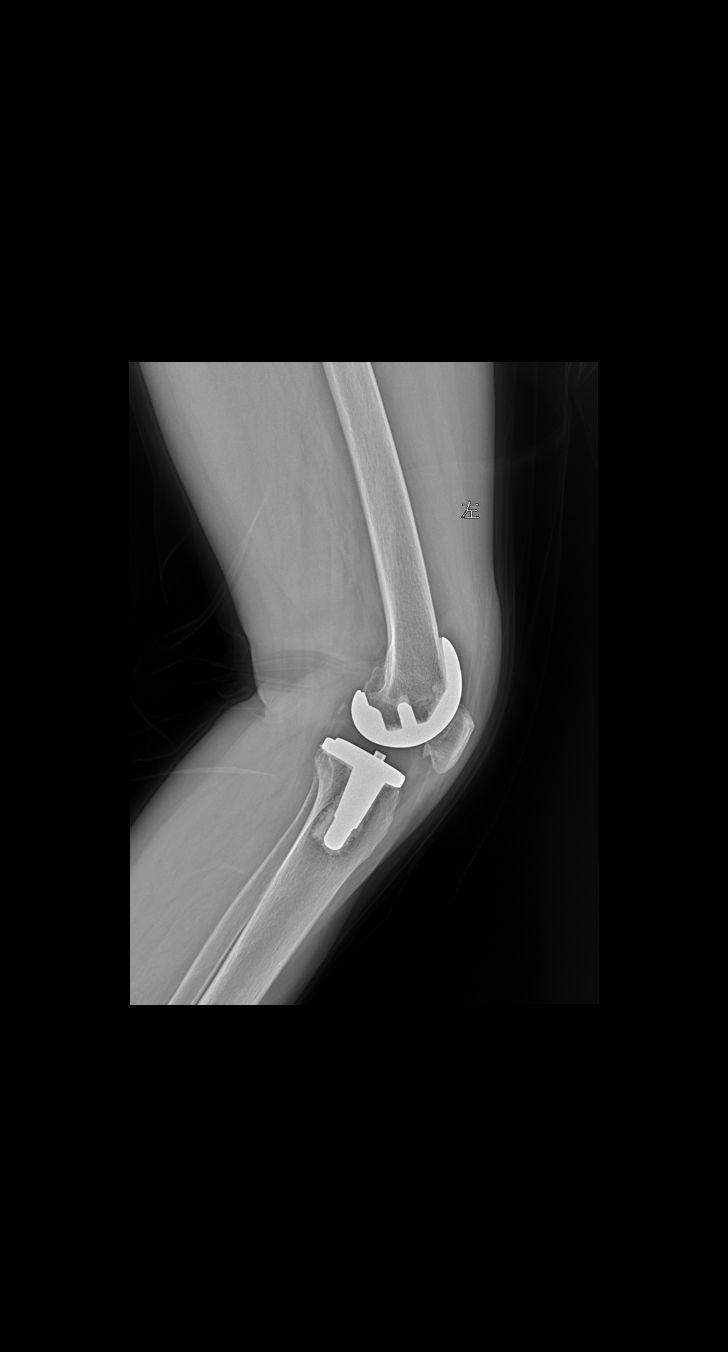

术后 复查 女61

2024-11-08 15:58:22